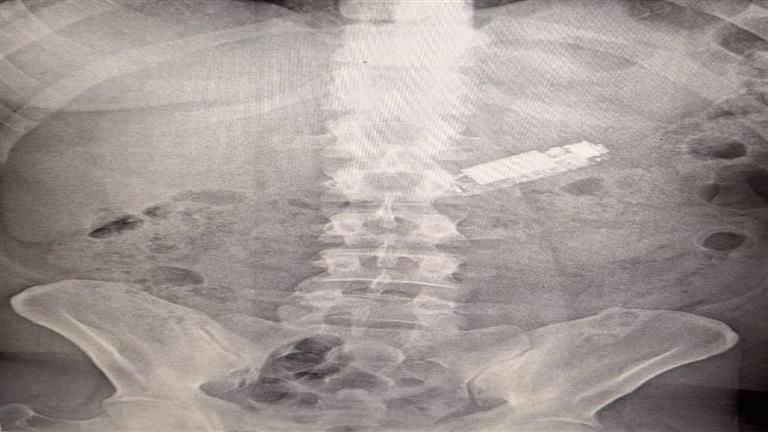

استدعت الحالة إجراء أشعة عادية على البطن لتحديد مكان الهاتف، وأكدت الأشعة وجوده في المعدة، وبعدما أجرى الفريق الطبي المتخصص عملية منظار على البطن استمرت لمدة ساعة، تمكنوا من استخراج الهاتف بنجاح، وخرج المريض من المستشفى في حالة صحية مستقرة.